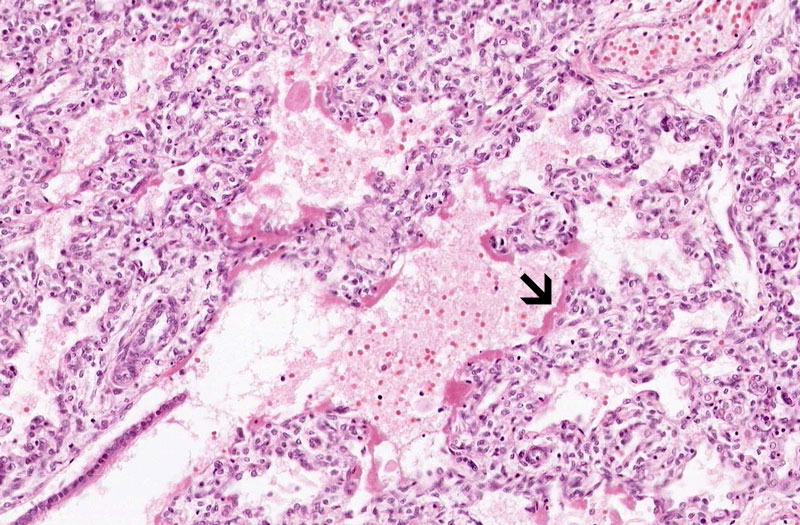

Area 3: This image is taken at the interface between the terminal bronchiole and the alveoli. Note the hyaline membrane lining the proximal air space (alveolar duct) highlighted by the arrow.

• Although the alveolar spaces are not completely expanded, distal airways and proximal air spaces (alveolar ducts) are usually dilated and lined by a thin layer of delicate, pale eosinophilic, amorphous transuduate-like substance known as hyaline membrane. The hyaline membrane may form within 30 minutes after birth.